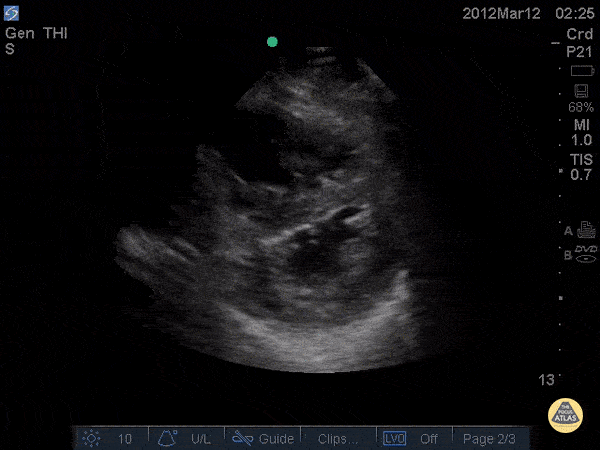

Right Ventricular Dysfunction - D-Sign in acute PE - Pre TPA

34 y/o female no PMH with chest pain and rapid onset dyspnea on exertion noticed over 1 day. Patient became increasingly tachycardic and ultimately hypotensive so RUSH exam was performed showing D - Sign. CTA was subsequently performed and found to have saddle emboli. Echo was done pre and post TPA showing partial resolution of the D-sign. Dr. Joshua Schechter - Kings County Emergency Medicine